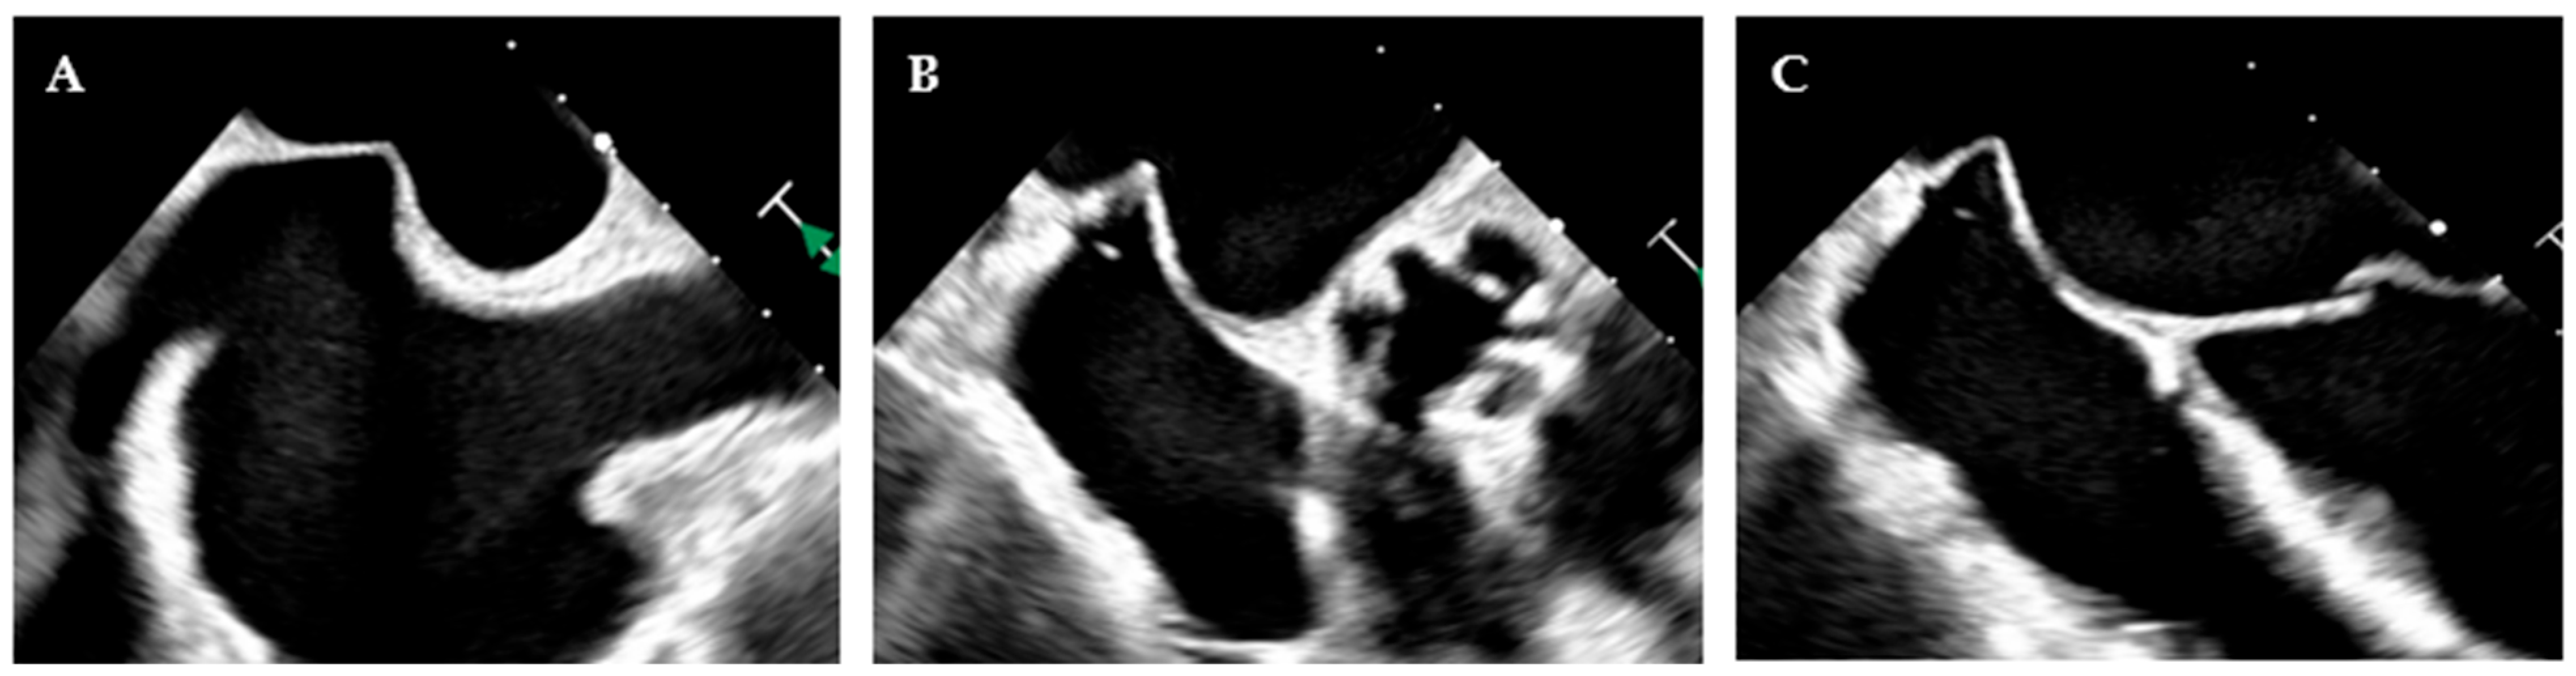

- Maslow, A.D.; Regan, M.M.; Haering, J.M.; Johnson, R.G.; Levine, R.A. Echocardiographic predictors of left ventricular outflow tract obstruction and systolic anterior motion of the mitral valve after mitral valve reconstruction for myxomatous valve disease. J. Am. Coll. Cardiol. 1999, 34, 2096–2104. [Google Scholar] [CrossRef]

- Varghese, R.; Itagaki, S.; Anyanwu, A.C.; Trigo, P.; Fischer, G.; Adams, D.H. Predicting systolic anterior motion after mitral valve reconstruction: Using intraoperative transoesophageal echocardiography to identify those at greatest risk. Eur. J. Cardio-Thorac. Surg. 2014, 45, 132–138. [Google Scholar] [CrossRef]

- Mihaileanu, S.; Marino, J.P.; Chauvaud, S.; Perier, P.; Forman, J.; Vissoat, J.; Julien, J.; Dreyfus, G.; Abastado, P.; Carpentier, A. Left ventricular outflow obstruction after mitral valve repair (Carpentier’s technique). Proposed mechanisms of disease. Circulation 1988, 78, I78–I84. [Google Scholar]